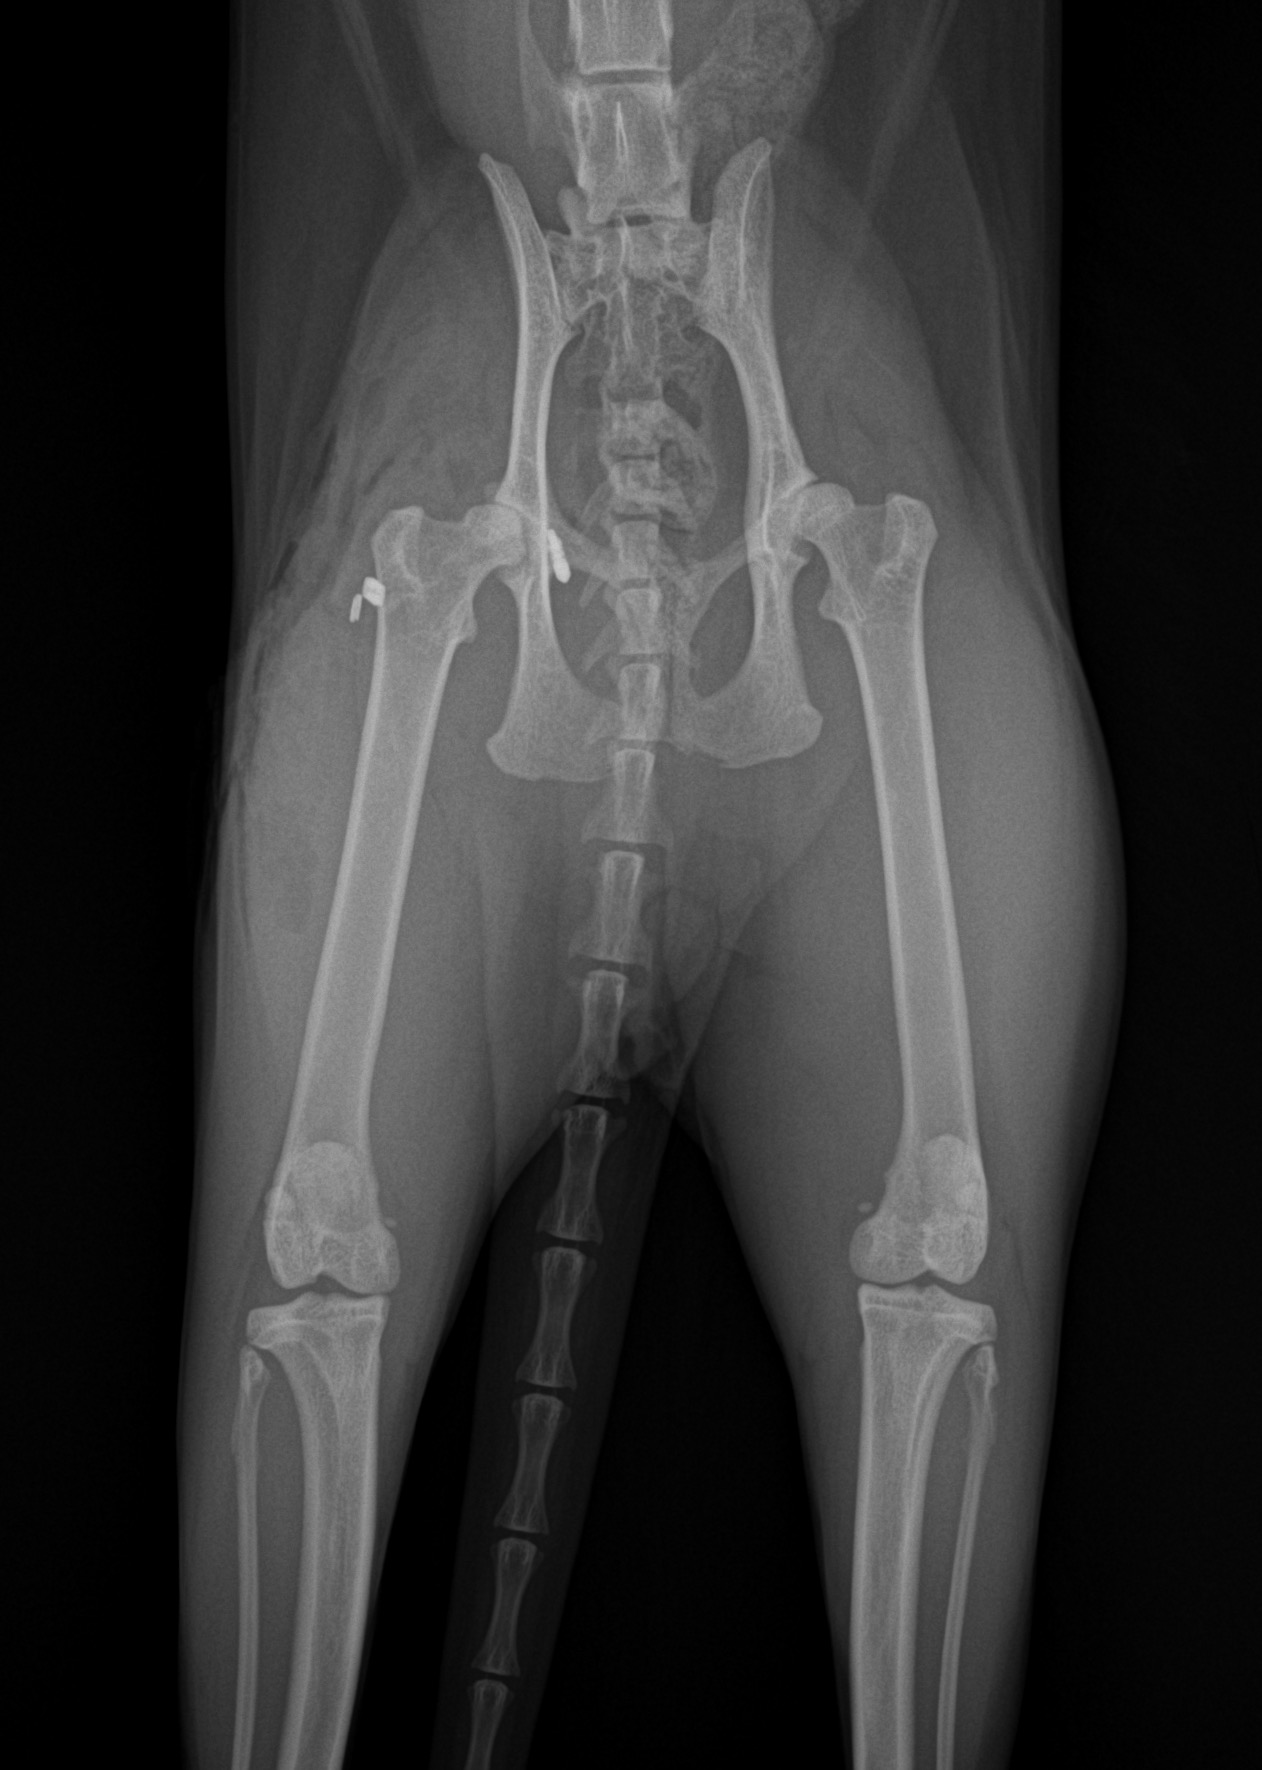

猫の股関節脱臼 外出から帰宅すると猫ちゃんが右後肢を跛行しているとのことで、救急で来院されました。エックス線では右股関節の背側前方脱臼が確認されました。トグルピンと人工靱帯により脱臼した大腿骨を寛骨内に整復します。しばらく安静が必要となります。 症例カテゴリー 放射線治療整形外科軟部組織外科脳神経外科内科腫瘍外科救急・集中治療リハビリテーション科腫瘍内科内視鏡科脳神経科呼吸器外科中医・漢方猫の腎移植循環器科